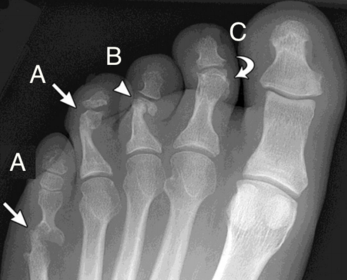

What disease is this? What is shown by A, B and C? | Psoriatic arthritis. A = destructive changes B = Pencil in cup deformity C = IPJ fusion |